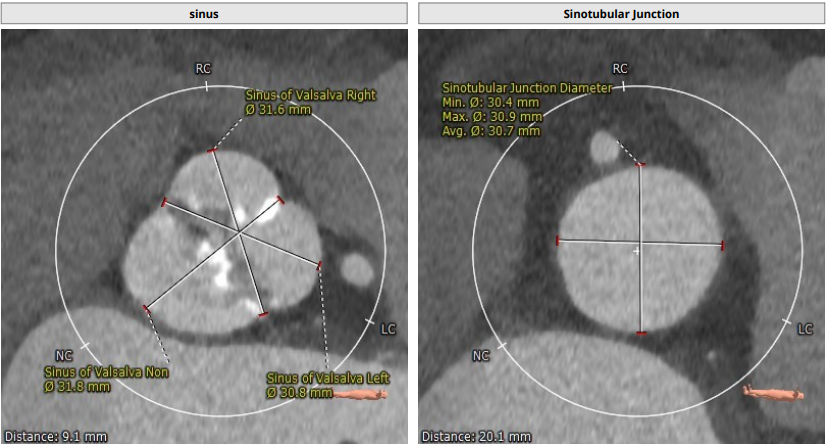

CT报告评估:

Annulus:24.4mm,LVOT:22.6mm,Asc.Ao:43.4mm,STJ:30.7mm。

LCA:10.7mm,RCA:15.0mm。

瓣环结构及钙化情况:患者为TYPE 1型二叶瓣,瓣环及左室流出道呈上宽下窄型结构,钙化积分为529,主要集中于无冠窦,从基底部开始延申至左右融合处及无冠窦游离缘,整体窦部空间合适。

心室情况:升主动脉增宽,心脏角度59°,严重心肌增厚,心室腔小。